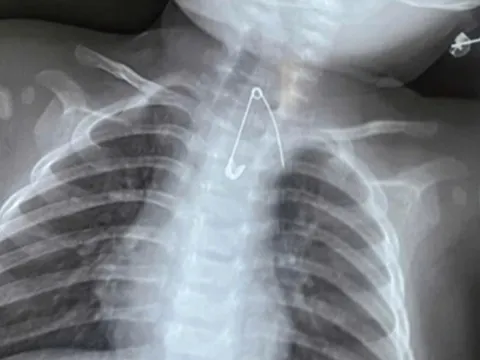

BS. Nguyễn Duy Anh cho biết, kết quả nội soi cho thấy khối u ung thư trực tràng đã phát triển lớn, chiếm trọn lòng trực tràng, gây tắc ruột hoàn toàn. Các bác sĩ buộc phải phẫu thuật cấp cứu làm hậu môn nhân tạo để giải phóng tắc nghẽn ruột cho bệnh nhân.

Tại thời điểm nhập viện, khối u gan di căn đã tăng kích thước lên hơn 10cm, xuất hiện nhiều nốt di căn ở cả hai phổi.